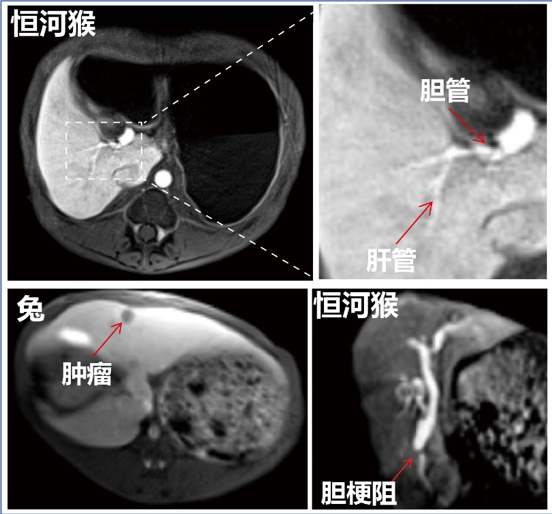

为获得大量、可靠的实验数据,樊海明与四川大学华西第二医院和中山大学附属第三医院合作,利用其磁共振成像设备开展大动物科学实验,数据表明,“玵立显®”可高特异性的靶向正常肝细胞,从而实现了早期肝癌微小病灶的精准影像检出;其肝对比度较临床特异性对比剂提高了5.8倍,可清晰分辨0.5毫米的肝管;肝胆期显影也从15分钟缩短到5分钟,显著提高了影像检查效率。更值得一提的是,“玵立显®”还能够通过肝胆代谢系统快速排泄,大幅减少了体内残留纳米颗粒带来的潜在副作用。